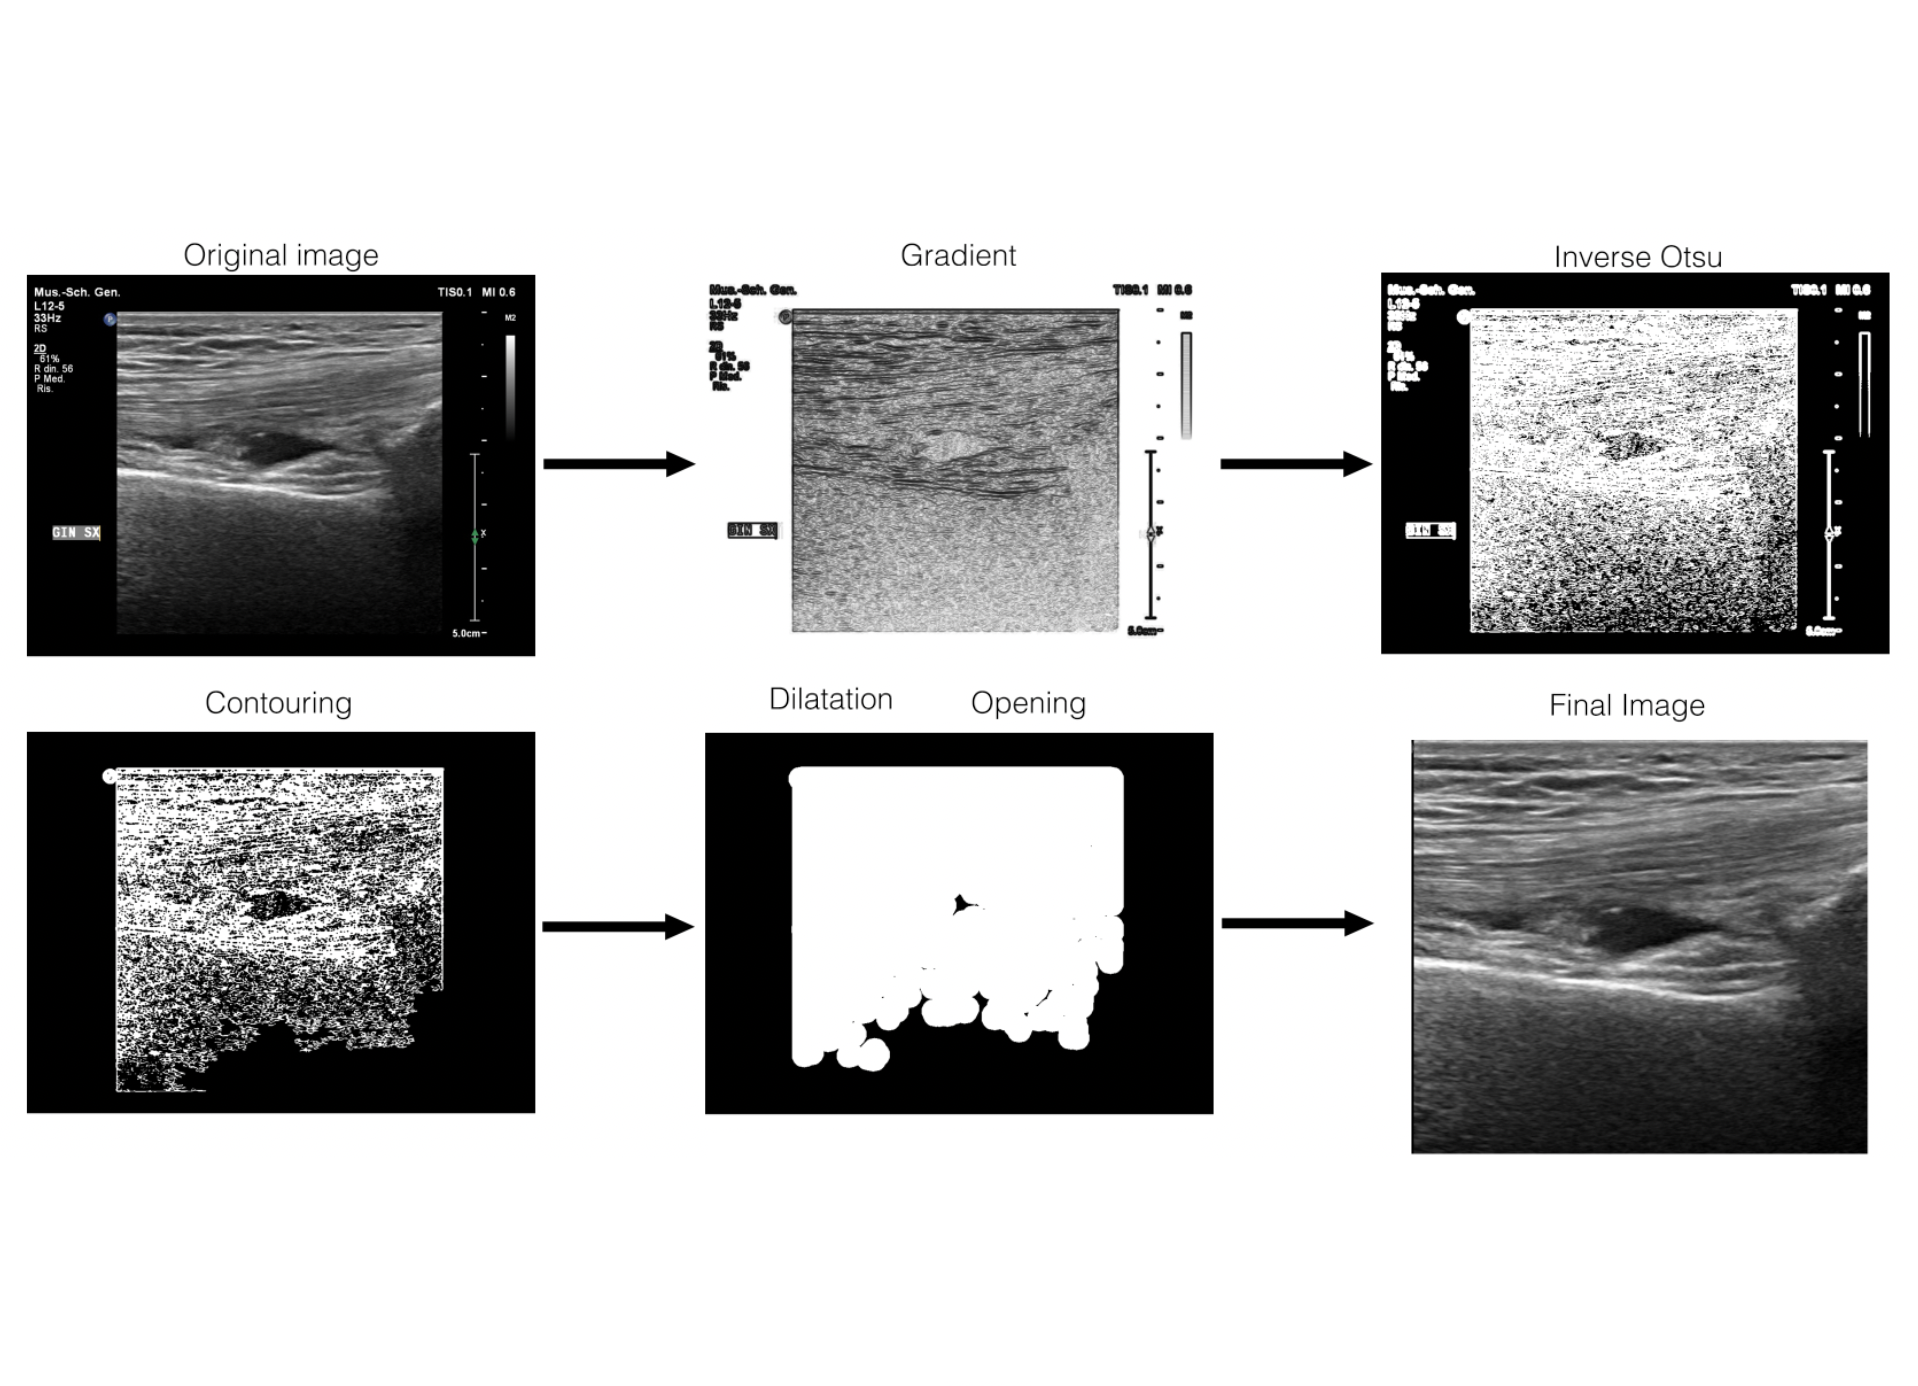

5.2 Pre-processing

We pre-process the collected images to extract the actual US image (e.g., the yellow box in Figure 1a). Indeed, as previously observed [45, 10] using the entire image as returned by the US device can reduce classification accuracy as this part of the image does not contain information needed for the required tasks.

As suggested by Tingelhoff et al [54] we initially cropped the images manually. However, this process is time consuming. We therefore developed an algorithm to automatically extract the US scan from the collected image. Figure 6 shows the steps of the pre-processing algorithm. In the first step, we measure and binarize the gradient of the image; we then remove connected pixel groups composed of less than 100010001000 non-zero pixels; afterwards, we dilate the image to fill small groups of black pixels, and we perform an opening operation to remove groups of pixels not belonging to the US scan that were merged with it in the previous steps. Finally we crop the original image with the bounding box of the white area resulting from the previous step. Finally the images are resized to 256×256256256256\times 256 pixels.

All images have been double-checked as part of the annotation process and no cropping error was found, showing that the proposed automatic pre-processing is reliable.

Refer to caption

Figure 6: Intermediate steps of frame extraction procedure